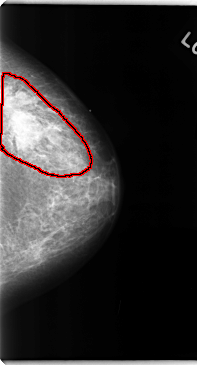

C_0108_1.LEFT_CC

LEFT_CC LINES 4744 PIXELS_PER_LINE 2560 BITS_PER_PIXEL 12 RESOLUTION 50 OVERLAY

FILE: C_0108_1.LEFT_CC.OVERLAY

TOTAL_ABNORMALITIES 1

ABNORMALITY 1

LESION_TYPE MASS SHAPE IRREGULAR MARGINS ILL_DEFINED

ASSESSMENT 5

SUBTLETY 5

PATHOLOGY MALIGNANT

TOTAL_OUTLINES 1

BOUNDARY